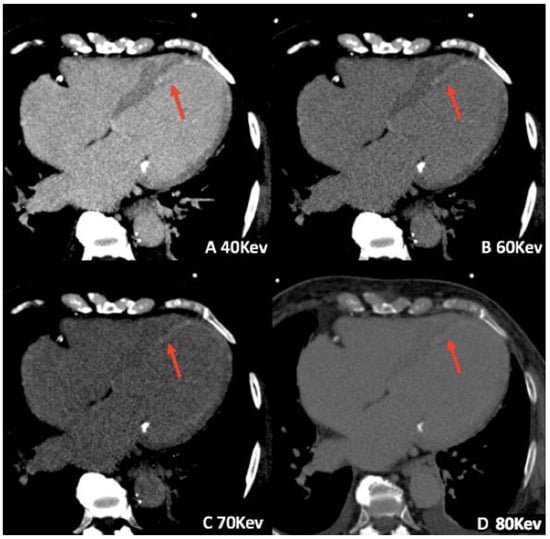

3.1. Virtual Monoenergetic Imaging (VMI)

- Zeng, Y.; Geng, D.; Zhang, J. Noise-optimized virtual monoenergetic imaging technology of the third-generation dual-source computed tomography and its clinical applications. Quant. Imaging Med. Surg. 2021, 11, 4627–4643. [Google Scholar] [CrossRef]

- Beeres, M.; Trommer, J.; Frellesen, C.; Nour-Eldin, N.-E.A.; Scholtz, J.E.; Herrmann, E.; Vogl, T.J.; Wichmann, J.L. Evaluation of different keV-settings in dual-energy CT angiography of the aorta using advanced image-based virtual monoenergetic imaging. Int. J. Cardiovasc. Imaging 2016, 32, 137–144. [Google Scholar] [CrossRef] [PubMed]

- Albrecht, M.H.; Scholtz, J.-E.; Hüsers, K.; Beeres, M.; Bucher, A.M.; Kaup, M.; Martin, S.S.; Fischer, S.; Bodelle, B.; Bauer, R.W.; et al. Advanced image-based virtual monoenergetic dual-energy CT angiography of the abdomen: Optimization of kiloelectron volt settings to improve image contrast. Eur. Radiol. 2016, 26, 1863–1870. [Google Scholar] [CrossRef]

- Chang, S.; Han, K.; Youn, J.-C.; Im, D.J.; Kim, J.Y.; Suh, Y.J.; Hong, Y.J.; Hur, J.; Kim, Y.J.; Choi, B.W.; et al. Utility of Dual-Energy CT-based Monochromatic Imaging in the Assessment of Myocardial Delayed Enhancement in Patients with Cardiomyopathy. Radiology 2018, 287, 442–451. [Google Scholar] [CrossRef] [PubMed]

- Wichmann, J.L.; Arbaciauskaite, R.; Kerl, J.M.; Frellesen, C.; Bodelle, B.; Lehnert, T.; Monsefi, N.; Vogl, T.J.; Bauer, R.W. Evaluation of monoenergetic late iodine enhancement dual-energy computed tomography for imaging of chronic myocardial infarction. Eur. Radiol. 2014, 24, 1211–1218. [Google Scholar] [CrossRef] [PubMed]

- Lenga, L.; Albrecht, M.H.; Othman, A.E.; Martin, S.S.; Leithner, D.; D’Angelo, T.; Arendt, C.; Scholtz, J.-E.; De Cecco, C.N.; Schoepf, U.J.; et al. Monoenergetic Dual-energy Computed Tomographic Imaging: Cardiothoracic Applications. J. Thorac. Imaging 2017, 32, 151–158. [Google Scholar] [CrossRef]